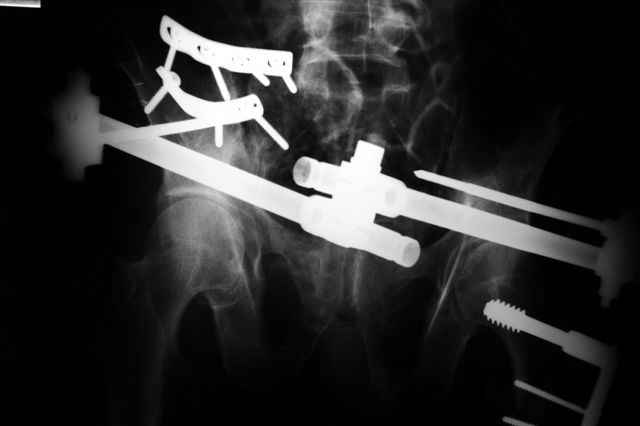

В приложении послеоперационные картинки.